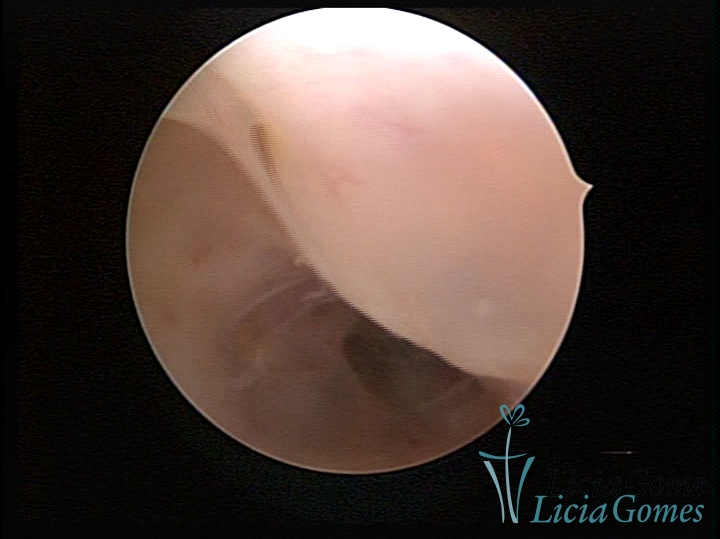

Sinéquia TIPO FIBROSA

As Sinéquia uterinas são cicatrizes (aderências) entre as superfícies das paredes uterinas, que podem ocorrer após manipulação cirúrgica, ou curetagem uterina, ou após um processo inflamatório na cavidade uterina (endometrite), podendo levar a alterações menstruais, infertilidade, e complicações obstétricas, como abortamento, parto prematuro.